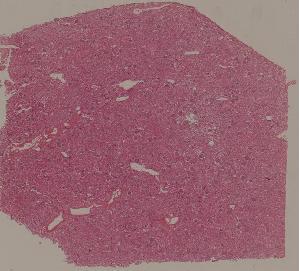

72. Membranous glomerulonephritis